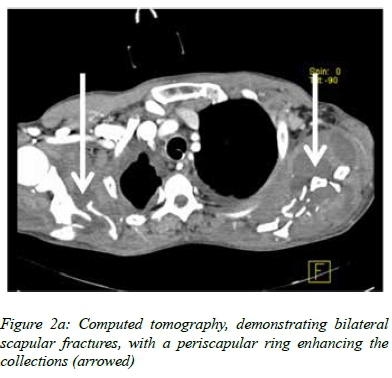

A 49-year-old man, who had fallen from a tractor and subsequently been run over by the same vehicle, sustained multiple injuries. An early VAP, due to Staphylococcus aureus, was treated successfully with cloxacillin. One week later, he developed a swinging pyrexia, which failed to settle, despite changing the vascular catheters, resampling the sputum and urine, taking numerous random blood cultures, and commencing directed therapy for Candida albicans in a tracheal aspirate and empirical meropenem. The CT suggested ring-enhancing lesions of both scapulae (Figure 2a) and the right iliac crest. However, serous fluid only, with no cultured organisms, was shown by aspiration of the latter. The PET/CT scan demonstrated maximal uptake around the comminuted fracture of the left scapula (Figure 2b), from which pus was aspirated. Twenty millilitres of frank pus and necrotic bone were removed during formal drainage under anaesthesia, the culture of which grew S. aureus sensitive to cloxacillin. Valvular lesions were not demonstrated on echocardiography. The fever subsided, and the patient was discharged 50 days after referral.

Gram-positive metastatic sepsis is difficult to locate because of a paucity of symptoms and localising signs. Early identification is crucial as extended antimicrobial therapy or surgical drainage may be required for these foci, failing which the relapse and mortality rates are significantly higher.10 Given that all the fractures in our patients were closed, and cloxacillin-sensitive S. aureus was isolated from a tracheal aspirate, and subsequently from the scapular abscess, it would appear that the scapular collection arose as a result of bacteraemia and a metastatic staphylococcal deposit. CT scanning alone failed to identify the exact source, as evidenced by the initial aspirate from the fluid collection around the iliac crest. The addition of PET pinpointed the specific location. This emphasises the benefit of this hybrid approach, where CT defines the anatomy, and PET the metabolic activity. An echocardiography was used to exclude valvular disease, as recommended in patients with metastatic Gram-positive infections.11

Although used predominantly in non-critically ill patients with a fever of unknown origin, the few studies which have addressed its use in intensive care have been extremely promising, reporting both positive and negative predictive values of 90%.3,13 These studies have addressed pyrexia of unknown origin in a general ICU population, and a word of caution is necessary with regard to the critically injured, where increased metabolic activity at the fracture sites may result in a false positive scan.14 Fortunately, a comparison could be made with the opposite side in our patient with bilateral scapular fractures, and failed to demonstrate excessive 18F-FDG uptake.